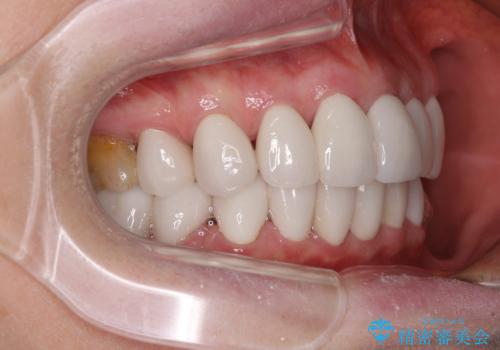

- 口元の突出感と歯の色を気にして来院された患者様です。

口元を引っ込めるために上下左右第一小臼歯4本を抜歯し、ワイヤー矯正を行うこととしました。

歯の色はホワイトニングかセラミッククラウンで対応することとしましたが、ブラックトライアングルが目立つことが予想されたため、目立つ範囲をオールセラミッククラウンで補綴することとしました。

矯正治療をせず、セラミッククラウンので口元の突出感を改善しようとしても、神経を取り除く必要があったり、口元の突出感はあまり改善されなかったりと、後悔する可能性が高くなります。